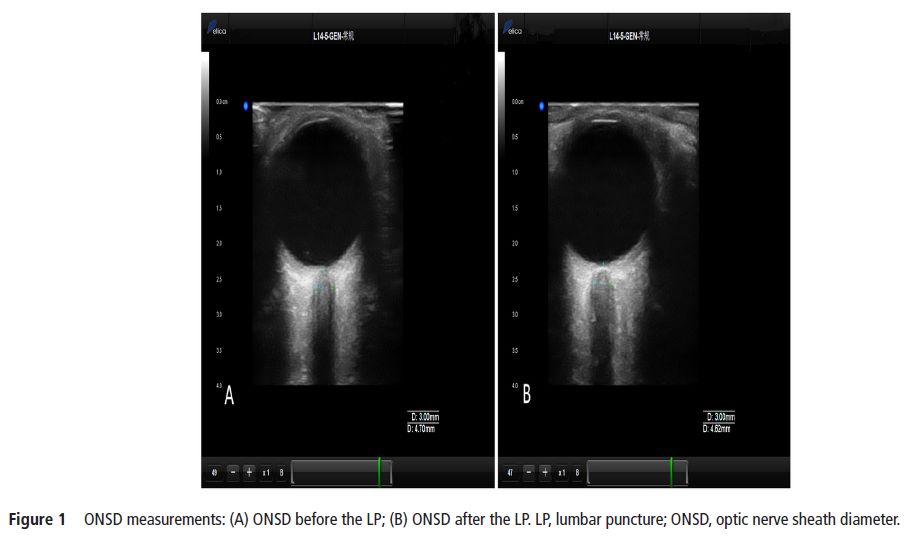

The current study aimed to identify whether ultrasonographic measurements of optic nerve sheath diameter (ONSD) could dynamically and sensitively evaluate real-time intracranial pressure (ICP). ONSD

measurements were performed approximately 5 min prior to and after a lumbar puncture (LP). A total of 84 patients (mean±SD age, 43.5±14.7 years; 41 (49%) men; 18 patients with elevated ICP) were included in the study. The Spearman correlation coefficients between the two observers were 0.779 and 0.703 in the transverse section and 0.751 and 0.788 in the vertical section for the left and right eyes, respectively. The median (IQR) change in ONSD (ΔONSD) and change in ICP (ΔICP) were 0.11 (0.05–0.21) mm and 30 (20–40) mmH2O, respectively, for all participants. With a reduction in cerebrospinal fluid pressure, 80 subjects (95%) showed an immediate drop in ONSD; the median (IQR) decreased from 4.13 (4.02–4.38) mm to 4.02 (3.90–4.23) mm (p<0.001). Significant correlations were found between ONSD and ICP before LPs (r=0.482, p<0.01) and between ΔONSD and ΔICP (r=0.451, p<0.01). Ultrasonic measurement of ONSD can reflect the relative real-time changes in ICP.【The ONSD was measured with the Delica MVU-6300 (Shenzhen, Guangzhou, China),】

【作者注:腰穿前后對比視神經(jīng)鞘變化,發(fā)現(xiàn)超聲檢測視神經(jīng)鞘直徑可以實(shí)時(shí)顯示顱內(nèi)壓改變,也進(jìn)一步證實(shí)了關(guān)于視神經(jīng)鞘研究的規(guī)范操作流程,應(yīng)該在腰穿之前進(jìn)行視神經(jīng)鞘測量】。